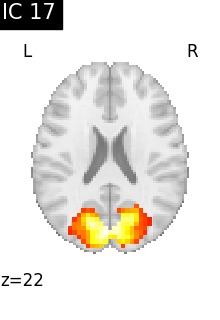

Finally, we plot the map for each ICA component separately

from nilearn.image import iter_img

from nilearn.plotting import plot_stat_map, show

for i, cur_img in enumerate(iter_img(canica_components_img)):

plot_stat_map(

cur_img,

display_mode="z",

title=f"IC {int(i)}",

cut_coords=1,

colorbar=False,

)